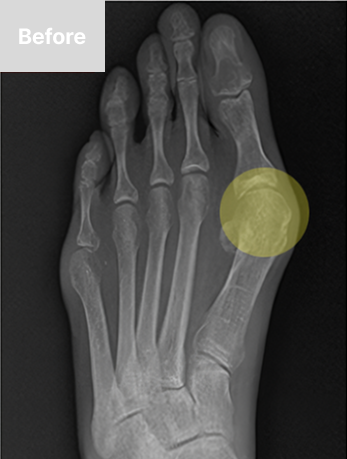

최소침습 무지외반 교정술이란?

경증에서 중등도의 무지외반증 환자를 대상으로,

환부에 약 2mm 크기의 구멍을 2~4개 뚫어 변형된 뼈를 교정하는 수술법입니다.

부분마취 후 최소 2mm 최소 피부절개(구멍2~4개)를 시행한 뒤, 실시간 방사선 영장장치 보면서

특수 기계를 넣어 변형된 뼈를 세밀하게 절골하고, 절골한 뼈를 올바른 배열로 배치합니다.

무지외반증

무지외반증이란 볼이 좁은 신발이나 하이힐을 자주 착용하는 여성에게서 주로 발생하며,

엄지발가락이 바깥쪽으로 휘어 관절 부위가 돌출되는 족부 질환입니다.

돌출된 엄지발가락으로 인해 걷는 데 불편함을 느끼고, 외관상으로 보기에도 좋지 않으며, 통증이 발생할 수도 있습니다.

무지외반증 치료방법

발가락 변형 정도에 따라 B-ita(바른마디병원 미타) 수술 혹은 근위부 교정술로 수술이 진행됩니다.